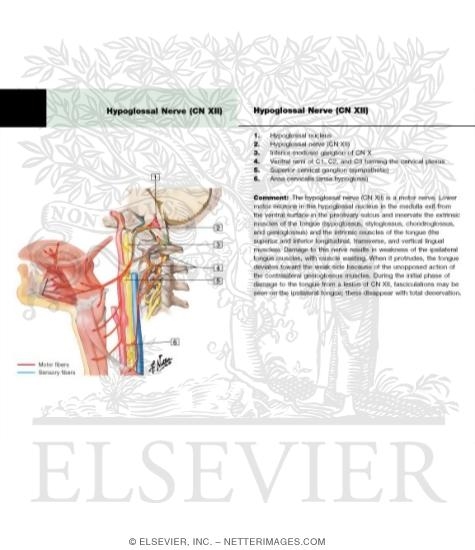

Hypoglossal Nerve (CN-XII)

Neuroanatomy, Cranial Nerve 12 (Hypoglossal) – StatPearls – NCBI Bookshelf

Hypoglossal Nerve (CN-XII)

Hypoglossal Nerve (CN-XII)

Hypoglossal Nerve (CN-XII)